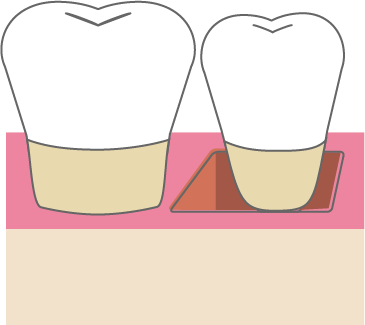

歯周組織再生療法は施術の難易度が高く、ほとんどの歯科では扱っていない内容です。

専門医資格を持つ医師が歯周組織再生治療を手がけるので、安心して治療を受けていただけます。